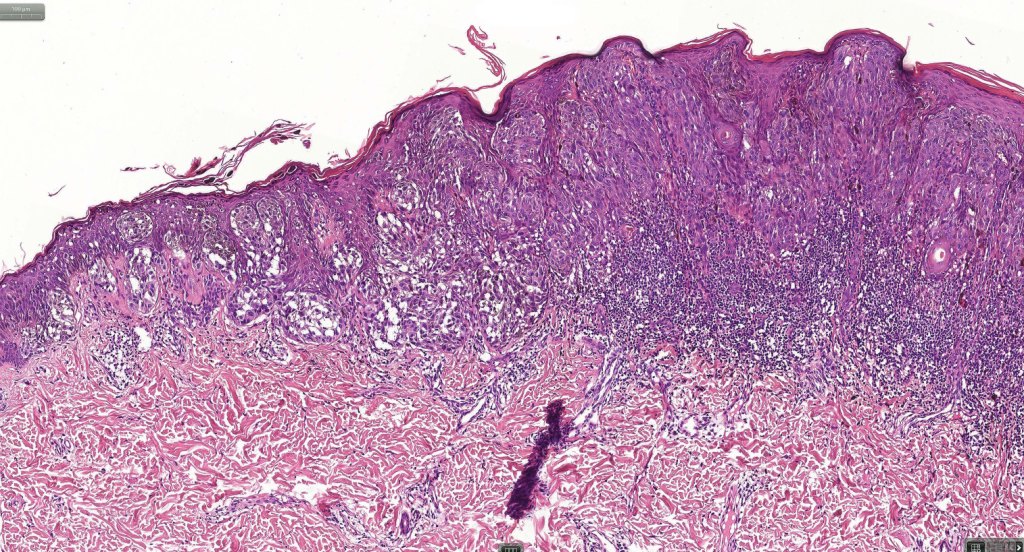

•Sharply circumscribed (begins and ends with a nest), symmetrical dome-shaped lesion. Symmetry is both horizontal and vertical (see image below)

•Wedge-shaped with the base uppermost or sometimes plaque-shaped silhouette

•Matures with depth-often best recognized at scanning/low power magnification & readily confirmed with S100 or MART1

•Hyperkeratosis & acanthosis, sometimes very marked

•Superficial vascular ectasia very frequently present

•Lymphocytic infiltration at the base of the lesion